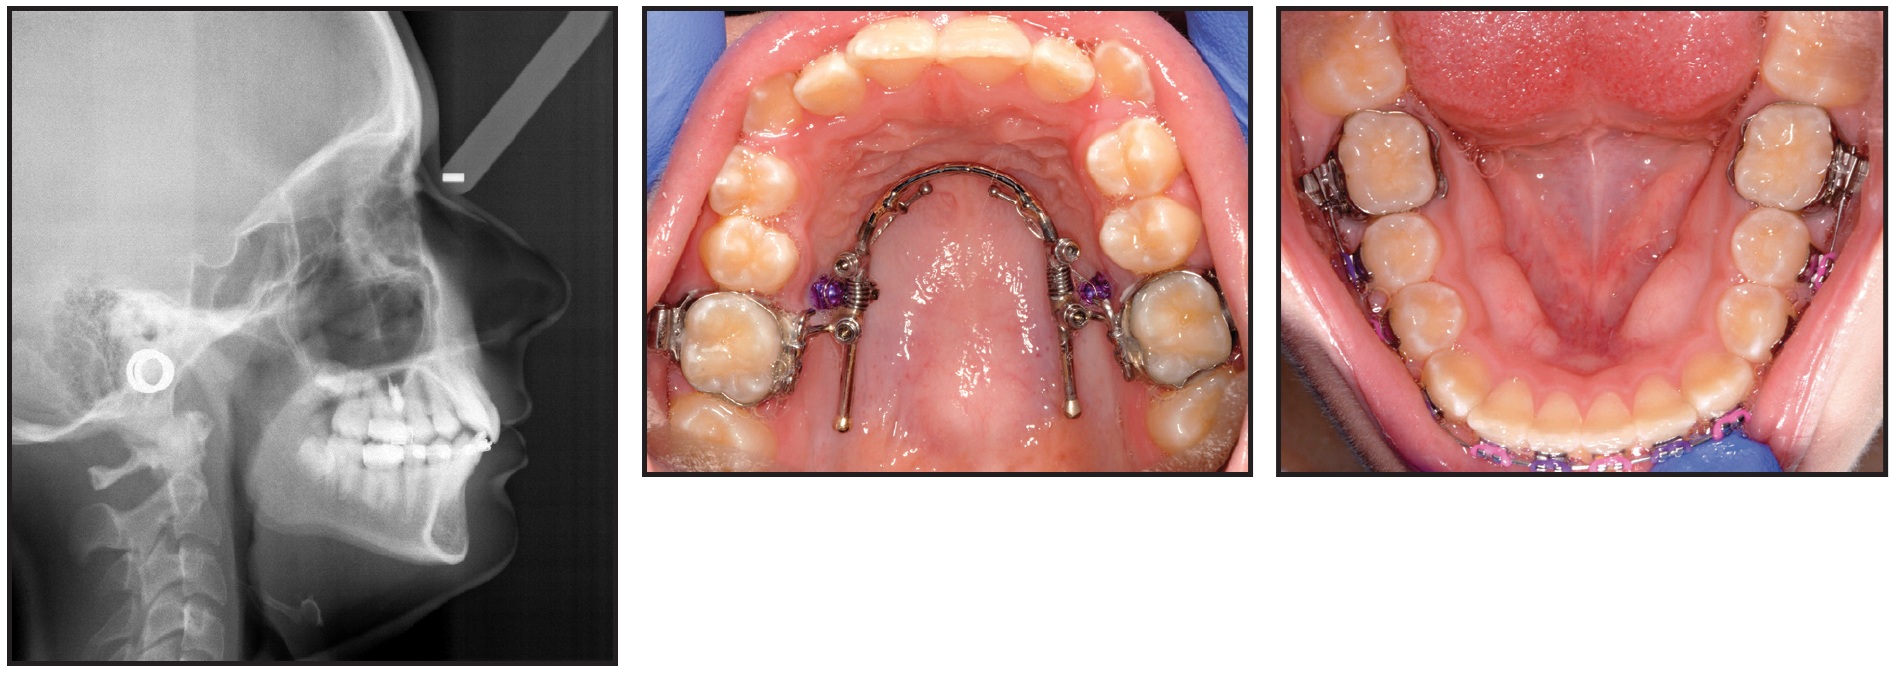

A Class I molar relationship was achieved in six months, with a movement rate of .8mm per month (Fig. 5).

Fig. 5 Class I molar relationship achieved after six months of treatment. AcceleDent use recorded as an average of 29 times per month.

The patient's use of vibration during that period was recorded as an average of 29 times per month. Treatment was completed in 16 months with 15 visits (Fig. 6).